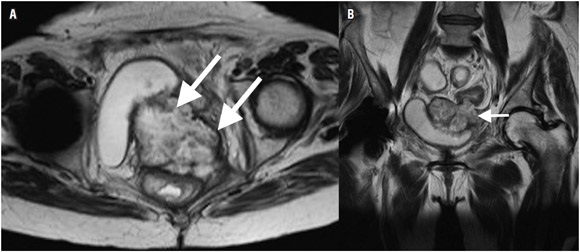

La recurrencia tumoral ocurre en el 70% en los primeros dos años y hasta en un 85% a los tres años (62,63). En los casos de recurrencia la resonancia magnética permite valorar la extensión de la enfermedad, así como el compromiso de órganos adyacentes (62), con una sensibilidad de 80% a 90% y una especificidad de hasta 100% (figura 8) (62,64-66). La recurrencia puede ser clasificada según la localización y el compromiso de estructuras en el plano axial (incluyendo recurrencia en la anastomosis y recurrencia local) en: anterior (involucra órganos localizados anteriores al recto en la pelvis como vejiga, útero, vagina, próstata y/o vesículas seminales), posterior (involucra estructuras localizadas posterior al recto como sacro, coxis o fascia presacra) y lateral (involucra estructuras localizadas lateral al recto como pared de la pelvis, vasos ilíacos, uréteres) (62,67).

Los cambios postquirúrgicos, el tejido de granulación, hematomas residuales, cambios inflamatorios inducidos por radiación y la radioterapia neoadyuvante, producen un aumento en la intensidad de señal en las secuencias con información T2 que puede llegar a ser indistinguible de una recurrencia tumoral (62,68). Este aumento en la intensidad de señal puede persistir hasta por 2 años luego del procedimiento quirúrgico (62,65). Debido a esto, el análisis morfológico y el realce con el medio de contraste se tornan esencialmente importantes para diferenciar los cambios postquirúrgicos de un tumor residual o recidivante. El tumor residual suele tener márgenes redondeados mientras que la fibrosis causa márgenes angulares o espiculados (62). En muchos centros diagnósticos se estima conveniente iniciar el seguimiento imagenológico, al menos 6 meses posteriores a la cirugía o a la última sesión de radioterapia. El uso de la secuencia en difusión mencionada anteriormente demuestra el beneficio para la detección del cáncer colorrectal (62,64) .